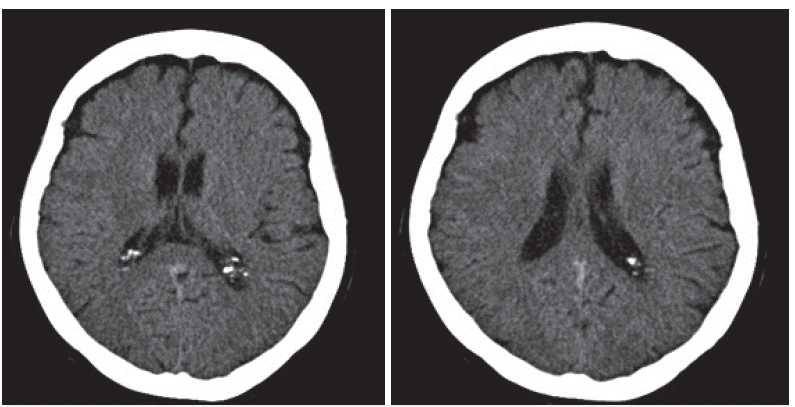

Al ingreso a la institución se considera que la paciente cursa con un cuadro clínico sugestivo de demencia rápidamente progresiva, se toma TAC (tomografía axial computarizada) simple, la cual no muestra áreas de isquemia, sangrado ni lesiones que ocupen espacio (figura 1).

TAC cráneo simple, imágenes en cortes axiales. No se identifica isquemia ni sangrado agudo, línea media conservada, no hay lesiones parenquimatosas que ocupen espacio.

Figura 1: TAC cráneo simple, imágenes en cortes axiales. No se identifica isquemia ni sangrado agudo, línea media conservada, no hay lesiones parenquimatosas que ocupen espacio.